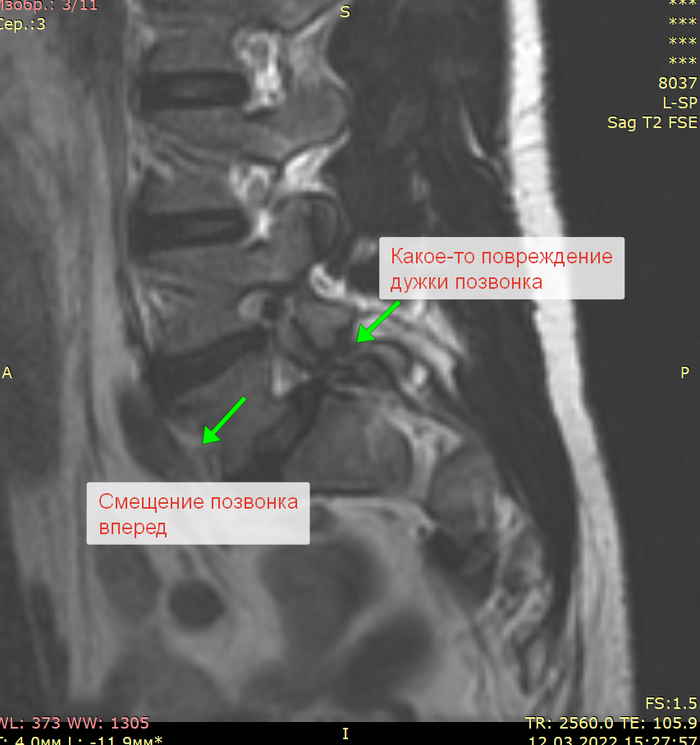

Смотрим улику №1 - МРТ.

Стрелками обозначены грыжи дисков.

тем кто в теме уже становится понятно - вряд ли дело в них.

Посмотрим нетипичную проекцию МРТ.

Получается проблема скорее всего на уровни костной ткани. Опять же, опытному специалисту уже все понятно, но мы продолжим.

Подозрения падают на такую штуку как спондилолистез (смещение) на фоне спондилолиза (незаращения дужек позвонка или их перелома).